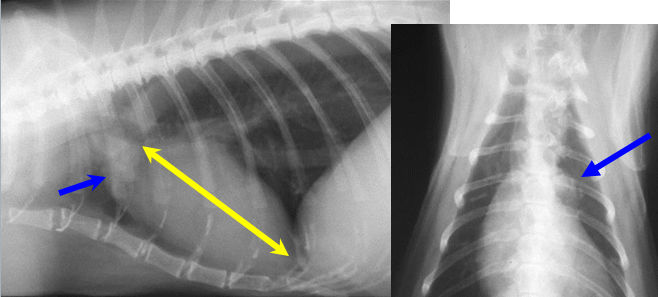

What is labelled here?

Yellow arrows: cranial mediastinum

Blue arrows – can see margins between 2 lung lobes as there is a fold of mediastinum going in between the 2 lung lobes and if this margin is transverse whilst doing a lateral view, will see it

What can be seen here?

Cranial mediastinum

Midline, homogenous soft band

Shouldn’t be any wider than twice the width of thoracic vertebrae